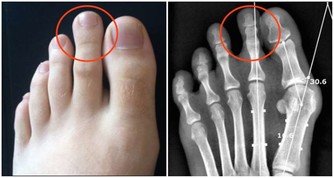

中醫認為人的手背經絡對應人體腰部,所以經常腰痛、腰酸的人,應該多拍拍手背。一手手掌拍另外一隻手的手背,交替拍即可。 這些方法簡單、實用,建議大家現在就做一次,刮刮手指,再拍拍手掌,每個動作重複20次,你一定會覺得身體清爽許多。 「新老人(微信號xinlaoren)」是中國最大的中老年人網站「楓網」官方微信,我們致力於關注您的健康和生活,為您提供最可靠、最精緻的閱讀服務。